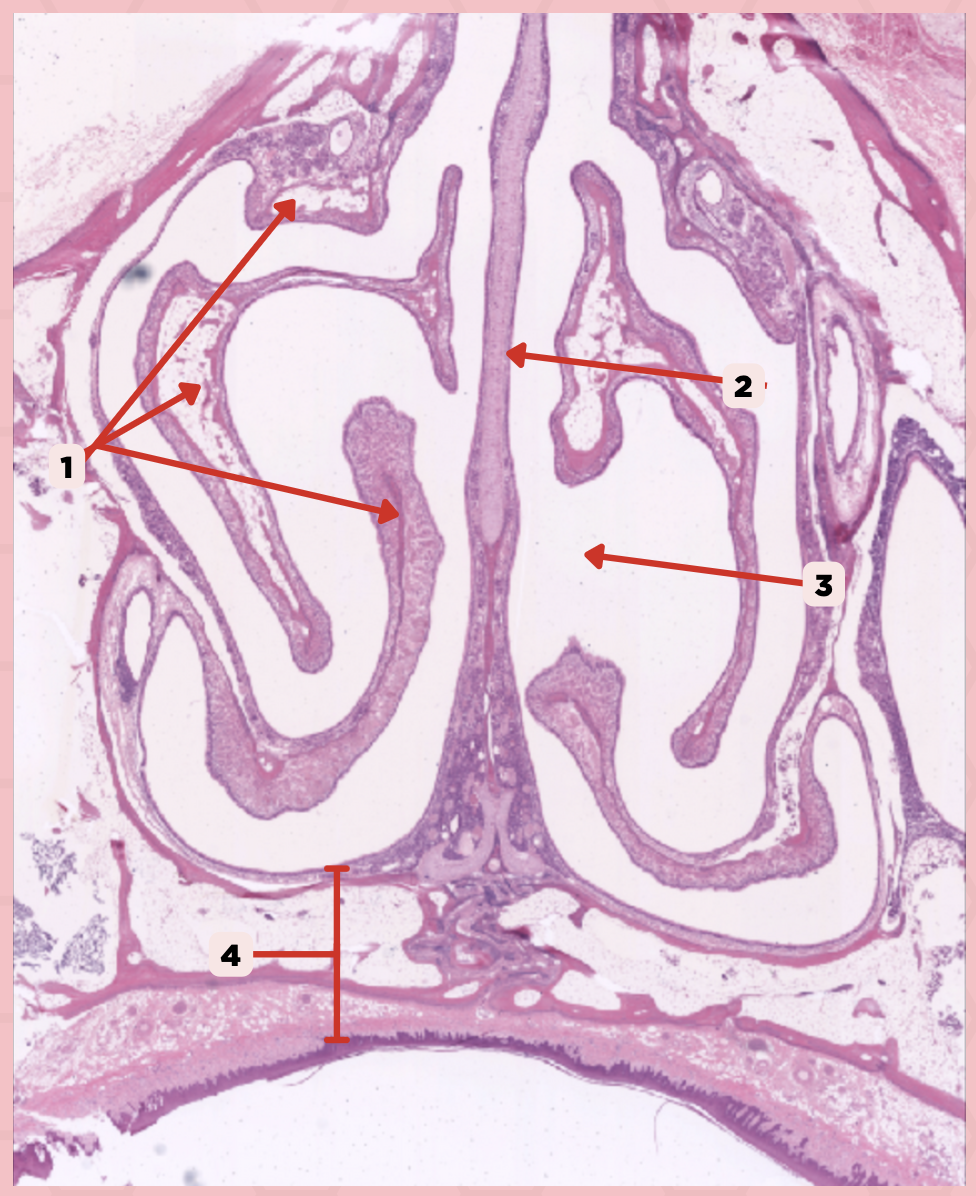

Nasal Cavity

What are the spaces found immediately lateral to #2?

Nasal Turbinates (conchae)

Identify the structure labeled as 1.

Nasal septum

Identify the structure labeled as 2.

Nasal cavity

Identify the structure labeled as 3.

Hard palate

Identify the structure labeled as 4.

Mucosal Associated Lymphoid Tissue (MALT)

What time of lymphocyte is numerous in the nasal cavity?